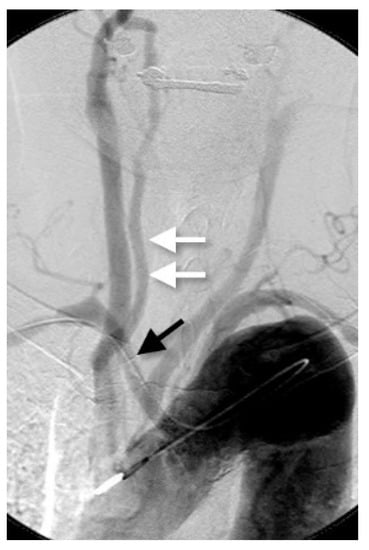

3.3. The Dual Origin of the Right Vertebral Artery